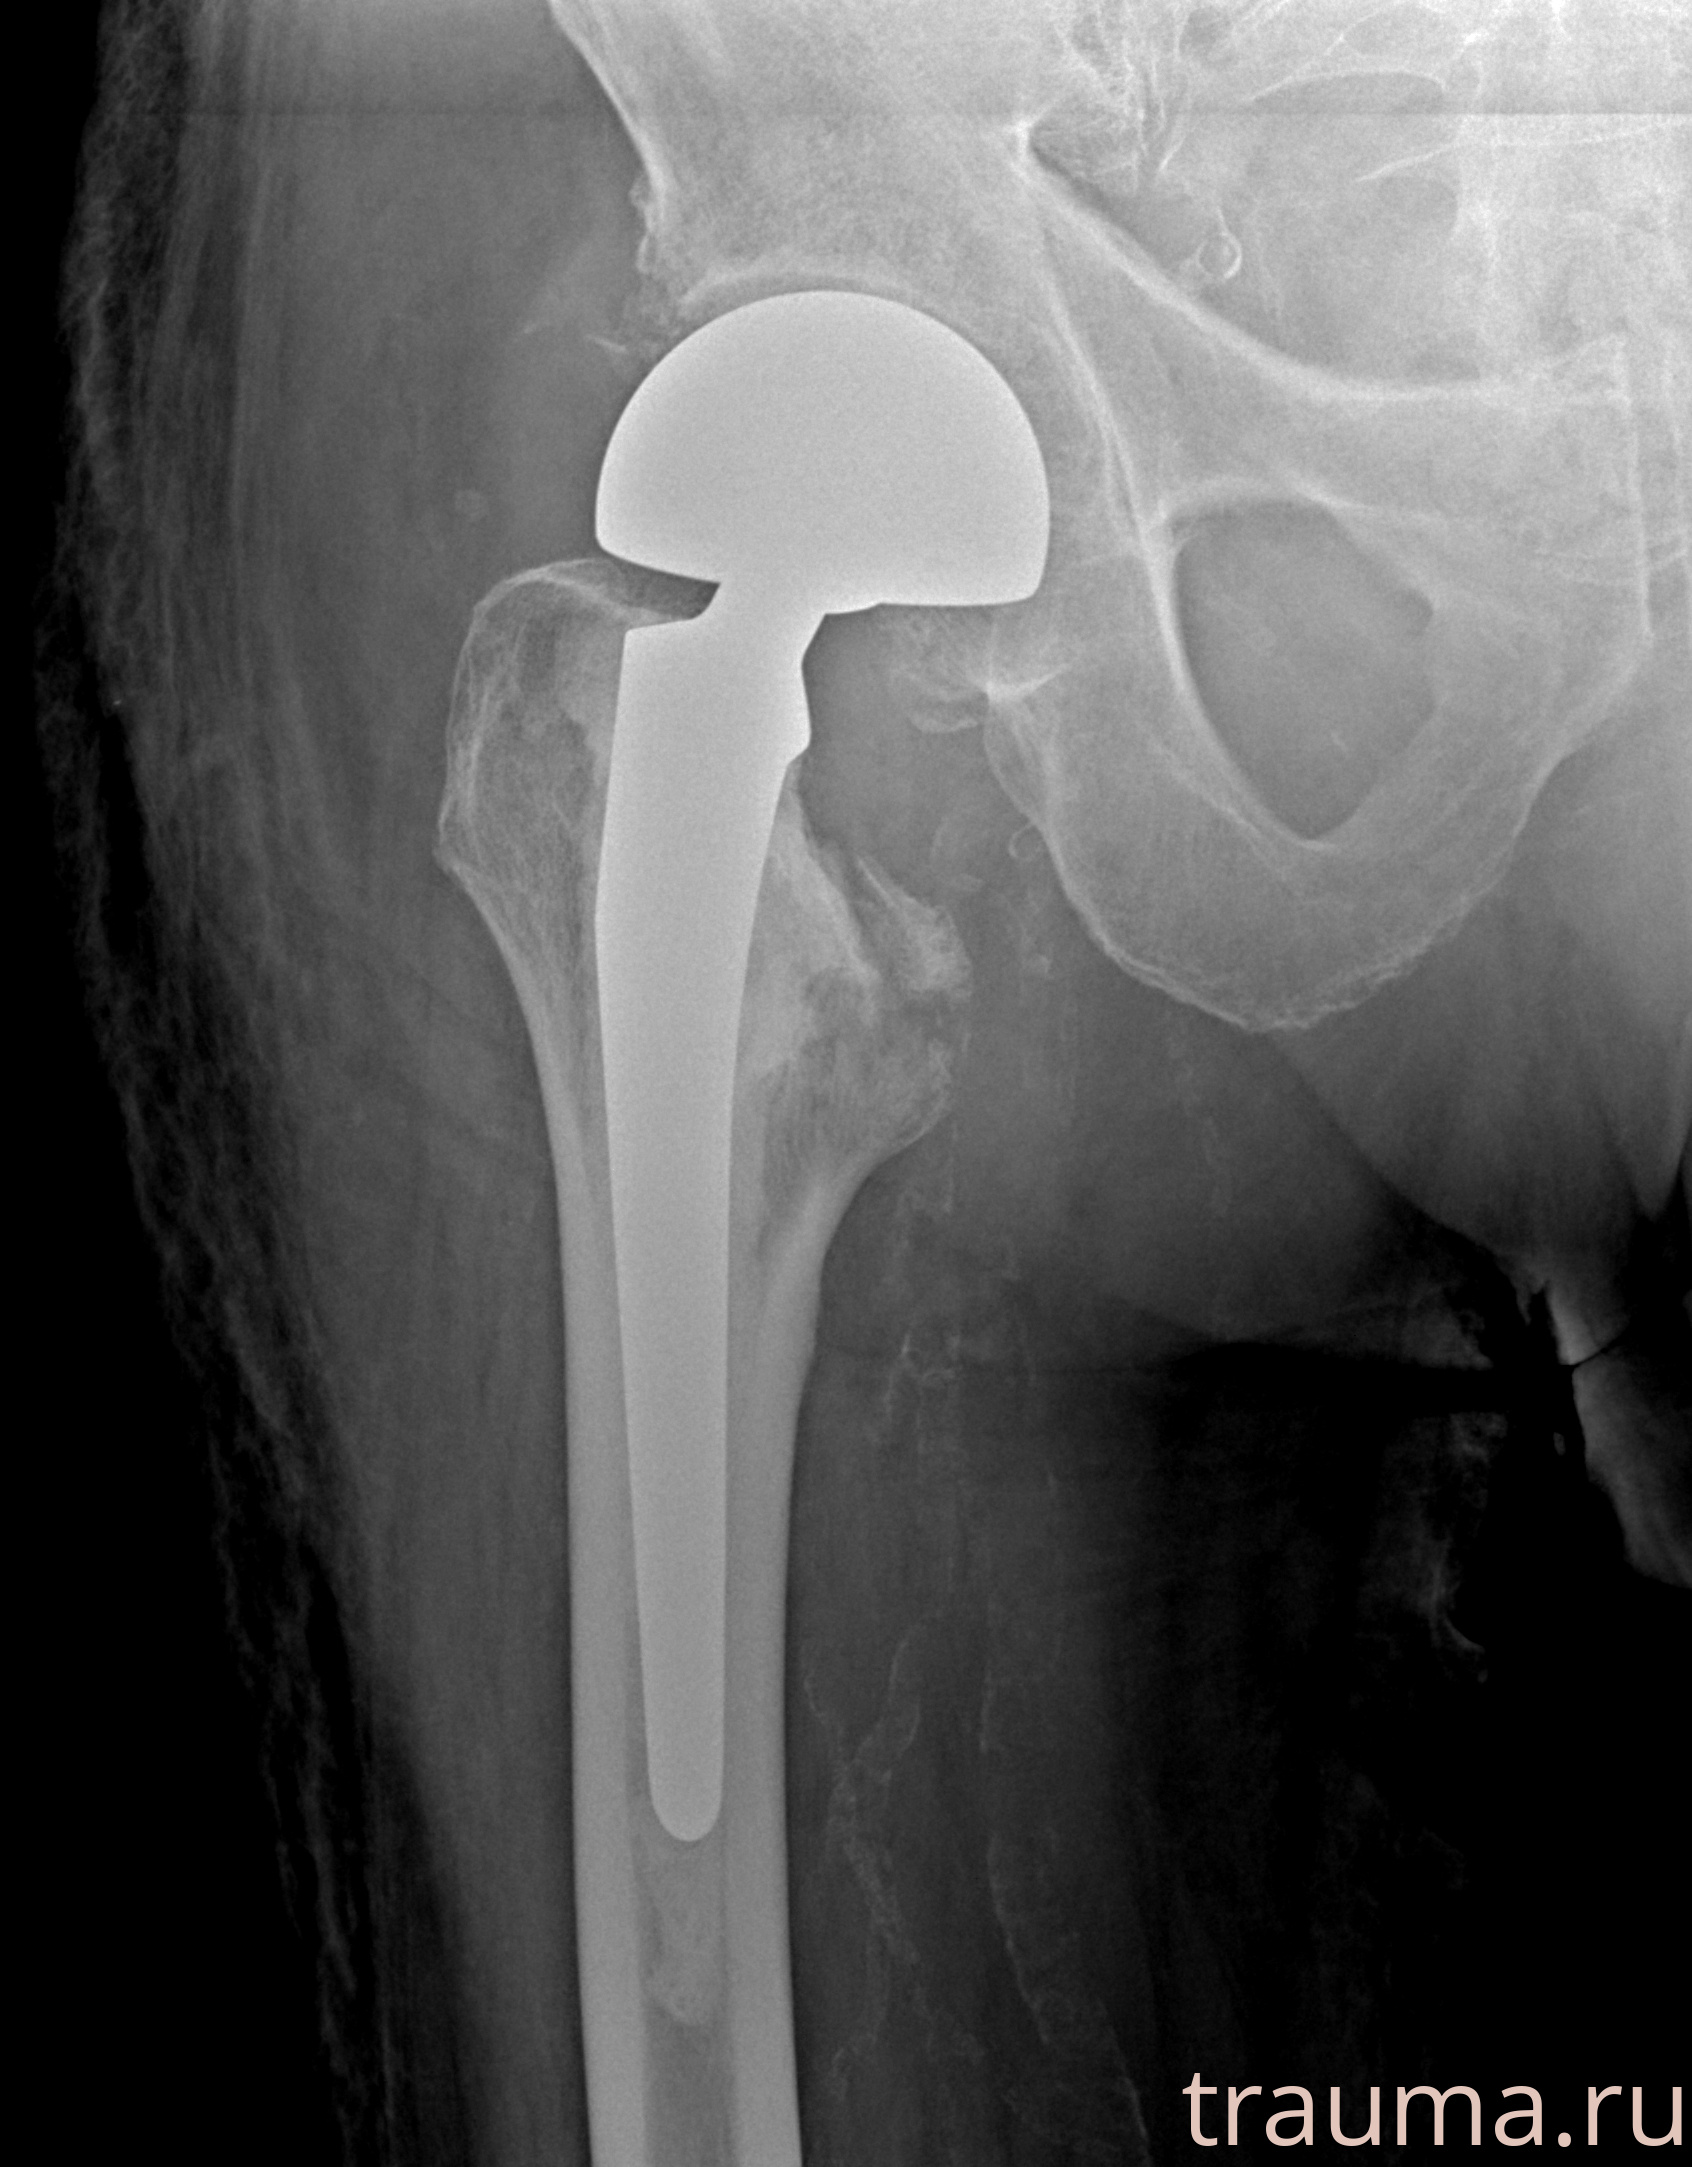

Рентгенограммы